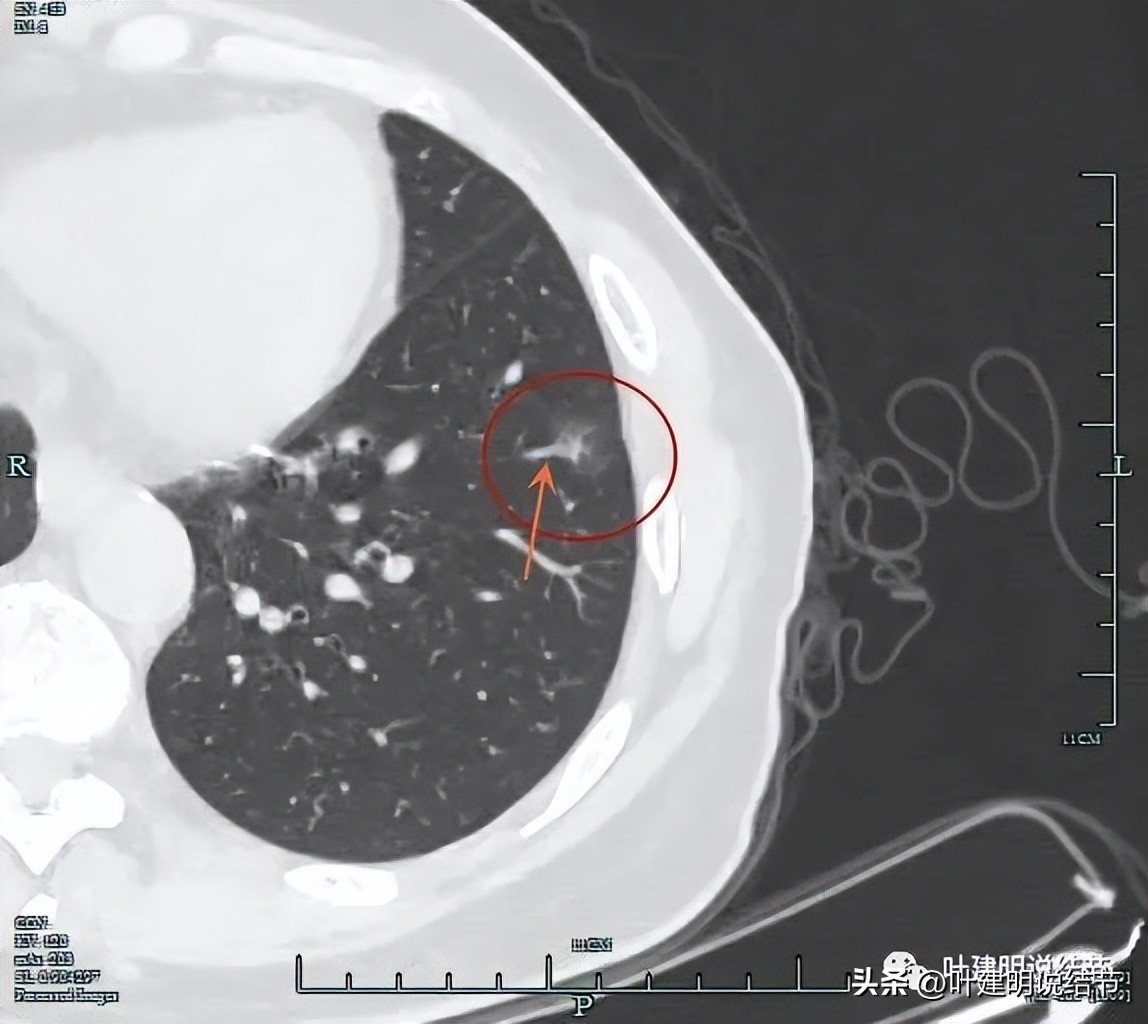

上图是右中叶的病灶,边缘偏模糊的磨玻璃影。因为最早于2018年时是报了右中叶有小结节,所以此处也要注意一下。

此灶中间有偏高密度,磨玻璃部分边缘不太清楚,显得瘤肺边界欠清。

灶内条状偏高密度可见。

叶间胸膜感觉略有点牵向病灶,但不厉害。

边缘区是磨玻璃成分,更靠胸膜处似乎还有卫星病灶。

右叶单按此次的影像来看,感觉倾向慢性炎些,毕竟收缩力弱、有卫星灶、轮廓虽清,但瘤肺边界欠清,磨玻璃部分密度较低,中间实性部分密度偏高但呈条状。